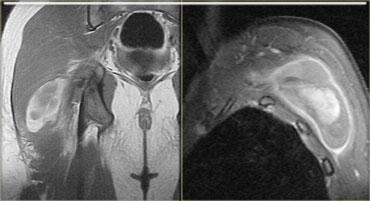

Bên trái là ví dụ về một tổn thương độ cao.

Có sự đứt hoàn toàn của gân hoặc chỗ nối cơ-gân của cơ ngực.

Bệnh nhân này sẽ mất hoàn toàn chức năng của cơ này.

Bên trái cho thấy hình ảnh rách hoàn toàn cơ gân kheo trái tại chỗ nối cơ-gân.

Các gân bị bong tróc và có sự tích tụ dịch.

Bên trái là một bệnh nhân khác cũng bị đứt hoàn toàn gân cơ hamstring.

Có hình thái phù nề ngoại mạc cơ và kích thích thần kinh tọa.

Có thể xảy ra hội chứng hamstring.

Đây là tình trạng đau do sự hình thành sẹo sau chấn thương xung quanh thần kinh tọa (mũi tên).